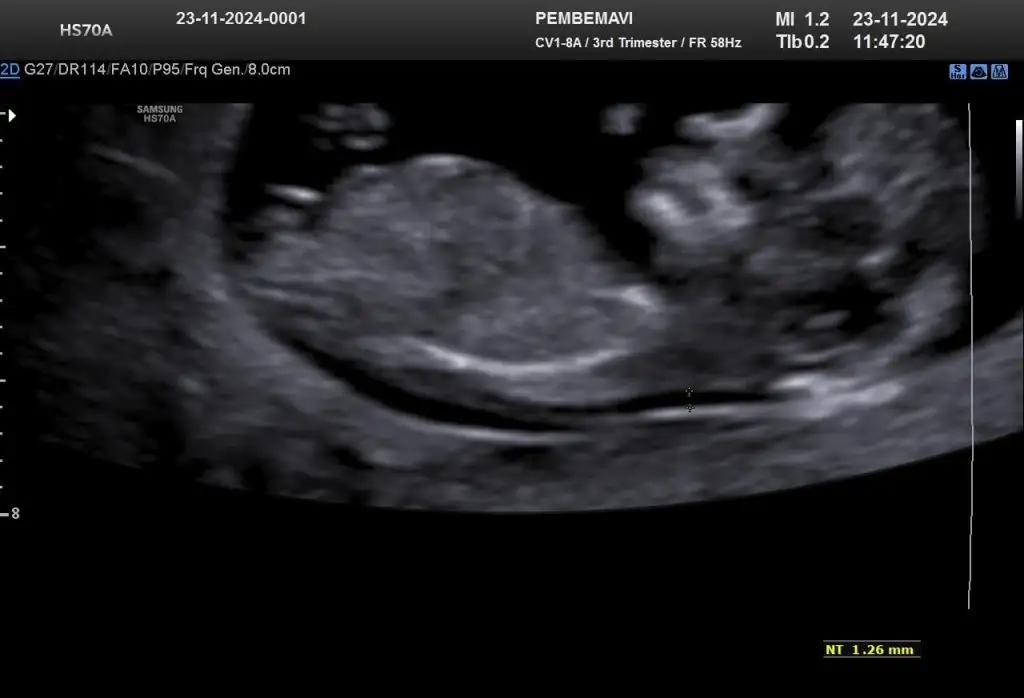

Gozun aydin canimBir kız da benden gelsinFetal DNA sonucum olumlu geldi çok şükür bir risk görünmüyor Cinsiyet için kız gibi demişti doktorum kesinleşmiş oldu ailemize bir prenses daha katılıyor

Ultrason resmin varmi, ureme organi nasildi veya baktiginda merak ettim. Bende kiza benzer anlik bir cikinti gordum gibi 2lide